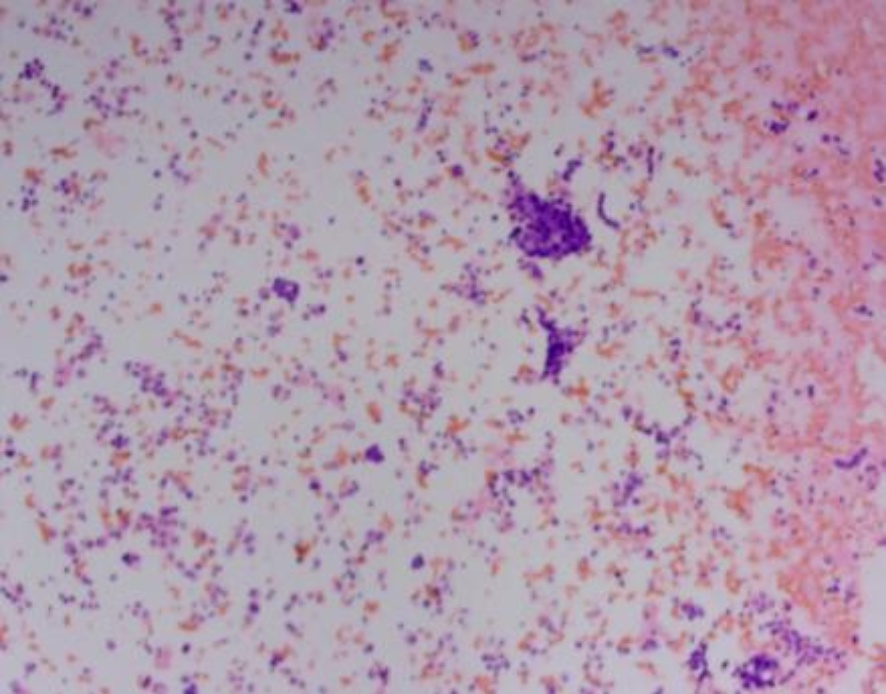

Figure 1. Intraoperative pathological image of pelvic effusion with HE staining

1. 术中盆腔积液病理图HE染色

经科室病案讨论分析,患者于2024年5月17日行剖腹探查术,探查见盆腔无粘连形成,可见淡黄色积液约200 ml,盆腔包块巨大、来自左侧卵巢、上缘达剑突、两侧达腋中线、多房、实性、触似橡皮感、灰白色,表面未见破口、左侧输卵管水肿、子宫大小尚可、右侧卵巢亦实性增大如拳头大小、表面光滑、灰白色、右侧输卵管外观未见明显异常,网膜、腹膜、肠管、肝脏、胃表面未见结节,盆腹腔未扪及肿大淋巴结,行左侧附件切除 + 右侧卵巢囊肿剥除术,手术切除左侧附件重量4.3 kg,右侧卵巢肿瘤大小约6 * 5 * 4 cm,待快速冰冻病理回报提示双侧均考虑卵巢无性细胞瘤,(腹水):镜下见淋巴细胞、中性粒细胞、增生间皮细胞及异型细胞。病情告知家属,征求其意愿行保留生育功能手术及腹腔留管备热灌注化疗。术后诊断双侧卵巢无性细胞瘤。5月20日顺铂方案腹腔热灌注化疗。分别于6月18日、7月9日、8月5日、9月2日给予依托泊苷 + 顺铂(EP)辅助化疗同时注射亮丙瑞林去势保护卵巢功能治疗,共化疗4周期,术后复查各项肿瘤标志物及各项辅助检查均未见异常,已随访17个月,患者目前生存状况良好,按照卵巢恶性肿瘤随访提示长期随访中。